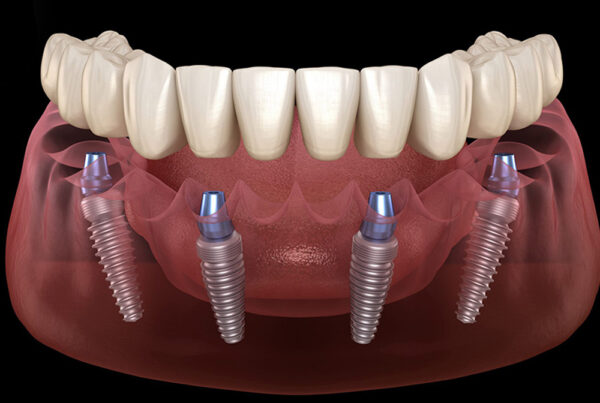

Zirkonyum kuron, olağanüstü gücü ve estetik nitelikleriyle bilinen bir malzeme olan zirkonyum oksitten yapılan bir diş kuronu türüdür. Bu kuronlar hasarlı, çürümüş veya zayıflamış dişleri kaplamak, şekillerini, boyutlarını ve işlevlerini geri kazandırmak için kullanılır. Ayrıca diş implantı restorasyonunun bir parçası olarak veya rengi solmuş veya şekilsiz dişlerin görünümünü iyileştirmek için de kullanılabilirler.

- Diş İmplantları: Eksik bir dişin yerini almak için bir diş implantının üzerine yerleştirilen bir kron olarak.

- Kuron Yerleştirme: Kuron hazır olduğunda, hazırlanan dişin üzerine yapıştırılarak işlevi ve görünümü geri kazandırılır.